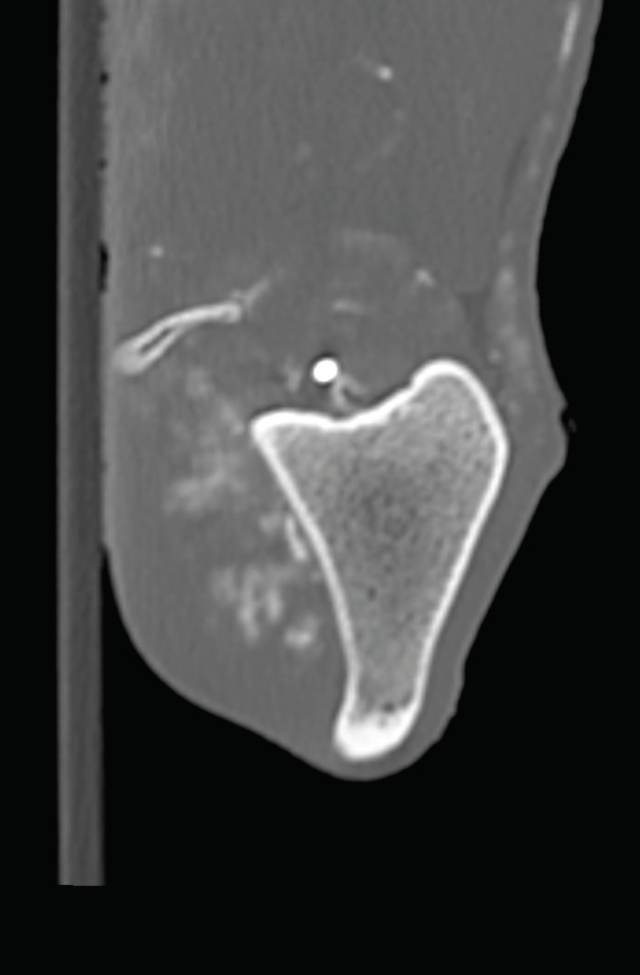

Proximity of the cranial tibial artery to the tibial bone at different angles of stifle extension in the dog: An ex vivo computed tomographic angiographic study

Cranial cruciate ligament disease (CCLD) is the most common cause of pelvic limb lameness in the dog. Tibial plateau levelling osteotomy (TPLO) is one of the most commonly performed procedures to treat CCLD by neutralising cranial tibial thrust and providing dynamic stability to the stifle joint at a standing angle. Excessive haemorrhage during the TPLO procedure has been described as an infrequent but potentially severe intraoperative complication, with a reported incidence of up to 1.6%. Damage to the proximal tibial musculature, cranial tibial artery or its five-way vascular network, or the cranial tibial vein during muscle elevation or performance of the osteotomy has been implicated as the cause of this excessive haemorrhage.1-6 In one study, the authors recommended performing the osteotomy with the stifle in flexion to allow the gastrocnemius muscle to relax and the cranial tibial artery to move caudally, potentially decreasing the risk of injury to the vessel during performance of the osteotomy. However, there have been no studies investigating the proximity of the cranial tibial artery to the tibial bone at different angles of stifle extension in dogs with intact or deficient cranial cruciate ligament. Therefore, the objectives of this study led by Dr Mullins are to: determine the shortest distance between the cranial tibial artery and the tibial bone at different angles of stifle extension in canine cadaveric stifles with an intact CCL and a completely transected CCL; and to investigate whether complete surgical transection of the CCL would result in a significant change in the distance between the cranial tibial artery and the tibial bone at any angle of stifle extension.